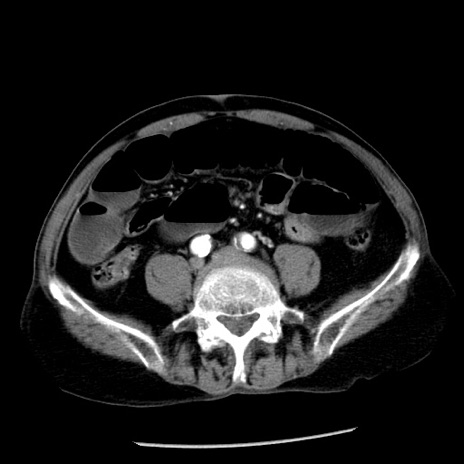

症例26(横断像)

【症例】80歳代男性

【主訴】嘔吐

【現病歴】昨晩2回嘔吐あり、今朝になっても嘔吐あり。来院。

【既往歴】胃潰瘍

【身体所見】意識清明、BT 37.6℃、BP 166/95mmHg、HR 100bpm、SpO2 97%、腹部:平坦・軟、腸蠕動音聴取良好、圧痛なし。

【データ】WBC 21900、CRP 1.46